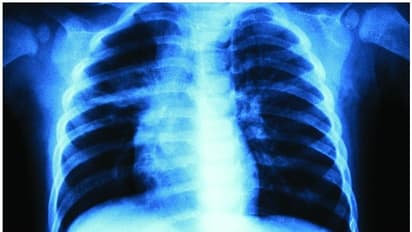

ദില്ലി: കൊവിഡ് 19 അഞ്ച് നിമിഷത്തിനുള്ളില് കണ്ടെത്താന് കഴിയുന്ന സോഫ്റ്റ്വെയര് കണ്ടെത്തിയെന്ന അവകാശവാദവുമായി ഐഐടി പ്രൊഫസര്. ഉത്തരാഖണ്ഡിലെ ഐഐടി റൂര്ഖിയിലെ പ്രൊഫസറുടേതാണ് അവകാശവാദം. എക്സ് റേ സ്കാനിംഗ് ഉപയോഗിച്ചാണ് വൈറസിന്റെ സാന്നിധ്യം സോഫ്റ്റ്വെയര് കണ്ടെത്തുന്നത് എന്നാണ് സിവില് എന്ജിനിയറിംഗ് വിഭാഗം പ്രൊഫസറായ കമാല് ജെയിന് അവകാശപ്പെടുന്നത്.

അറുപതിനായിരം എക്സ് റേ സ്കാനുകളുടെ ഡാറ്റാ ബേസ് പരിശോധിച്ച ശേഷമാണ് തന്റെ സോഫ്റ്റ്വെയര് കണ്ടെത്തല് എന്ന് പ്രൊഫസര് കമാല് പറയുന്നു. കൊവിഡ് 19, ന്യൂമോണിയ, ടിബി തുടങ്ങിയ രോഗികളുടെ നെഞ്ചിലുണ്ടാവുന്ന ബുദ്ധിമുട്ടുകള് വിവിധ തരത്തിലാണ്. അമേരിക്കയിലെ എന്ഐഎച്ച് ക്ലിനിക്കല് സെന്ററിലെ ഡാറ്റ ബേസ് ഗവേഷണത്തിനായി ഉപയോഗപ്പെടുത്തിയെന്നും പ്രൊഫസര് കമാല് പ്രതികരിക്കുന്നു.

വൈറസ് ബാധ സംശയിക്കുന്ന ആളിന്റെ എക്സ്റേ ഉപയോഗിച്ച് കൊവിഡ് 19ന്റെ സാന്നിധ്യം കണ്ടെത്താം. രോഗിക്ക് ന്യൂമോണിയ ഏത് ഘട്ടത്തിലാണെന്നും പ്രാഥമിക സ്ക്രീനിംഗില് അറിയാന് കഴിയും. വെറസ് ബാധമൂലമുള്ള രോഗലക്ഷണങ്ങളാണോ രോഗിക്കുള്ളതെന്നും പ്രാഥമിക ടെസ്റ്റില് തന്നെ കണ്ടെത്താന് സാധിക്കുമെന്നുമാണ് പ്രൊഫസര് കമാല് ജെയിന് വിശദമാക്കുന്നത്.